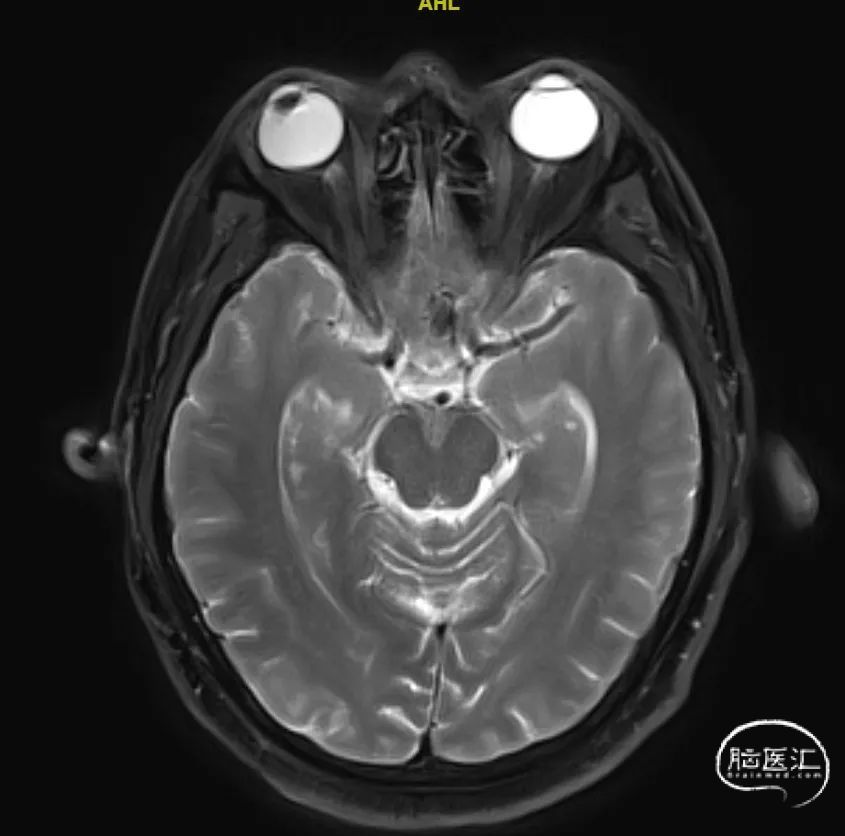

术前影像

CT及MRA:前交通动脉瘤。

造影显示:右侧Acom宽颈动脉瘤,大小约为7.5mm×10.5mm,动脉瘤底有双侧凸起,动脉瘤瘤颈宽,双侧A2段自动脉瘤侧壁发出。右侧A2起始直径1.7mm,左侧A2段起始部直径1.4mm。BOT试验显示左侧A1段不显影。